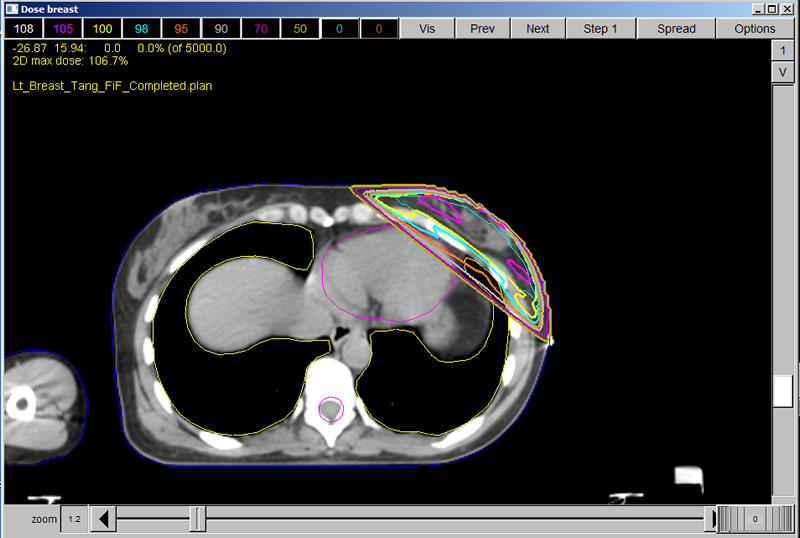

In the Directory, you will find other breast cases to practice on. Some of them will be completed cases so that you can see other techniques. There are many different ways to do treatment planning on breast cases. We have demonstrated wedges, but will also include a “Field in Field” case and an “IMRT” case for you to evaluate and practice on.